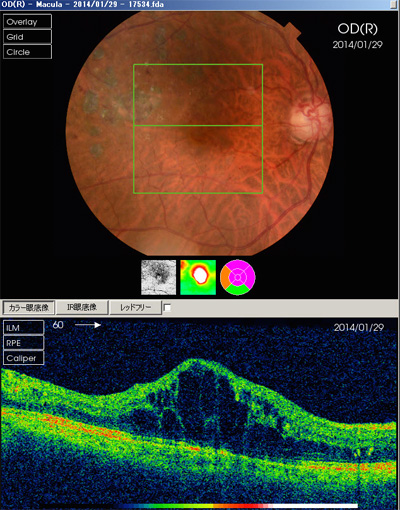

当院ではOCTを用いてより早期に緑内障を見つけるようにしています。

眼底検査で視神経乳頭の形状を診察するのが基本です。視神経乳頭陥凹があれば次に視野検査を行います。視野検査で異常があれば緑内障の確定診断となります。当院ではOCTという三次元眼底像撮影装置も用いて、緑内障の早期発見に努めています。

OCTは緑内障をおこす視神経の減少をより早期でとらえる事ができるので、早期診断、早期治療が必要な緑内障診療にはとても有用です。

加齢黄斑変性症の検査

加齢黄斑変性症の検査には以下のような物があります。

- OCT(網膜断層撮影)

検査は必要に応じて月1回、視力検査や眼底検査、OCT(光干渉断層網膜撮影)などをおこないます。